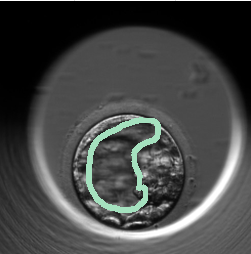

Figure 7 showcases examples of annotations made by embryologists on embryo images they perceived as synthetic, marking specific image regions or morphological features they identified as "fake." Several annotations focused around the ZP region, which is the outer layer surrounding the embryo. For instance, in Figure 7(a), despite the image depicting a real embryo, the embryologists could not clearly discern the boundary of the ZP, resulting in uncertainty about the image’s authenticity. Figures 7(b) and 7(c) display blastocyst-stage embryos. Figure 7(b) shows a real image that was mistakenly judged as fake because the trophectoderm—the outer cell layer that forms the placenta—was poorly visible due to darkness in the image, which misled the embryologists. In contrast, Figure 7(c) is a synthetic image correctly identified as fake, as it lacked the end of the trophectoderm, a clear indicator for embryologists. Figures 7(d) and 7(e) show sperm sitting on ZP with abnormal morphological structure leading embryologists to identify images as synthetic. To investigate the root cause, further training of our models on embryo images with unfused sperm on the ZP is recommended followed by an evaluation of the generated synthetic data.